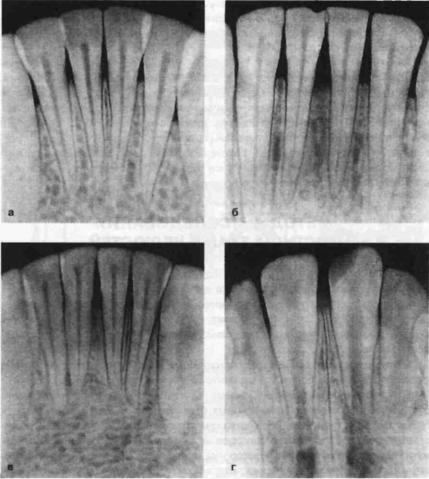

Анатомия: Межкорневая костная перегородка

Раздел: Галерея впечатлений